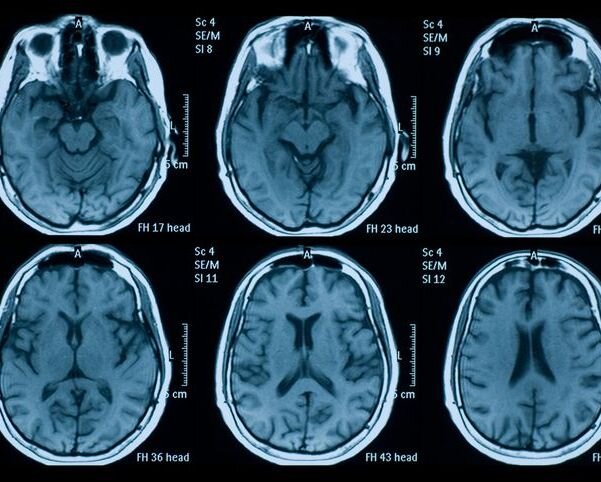

MRI scan of the brain

Around 40 million magnetic resonance imaging (MRI) scans are performed in the EU each year. The number of examinations is unevenly distributed among the member states, to such an extent that the number of MR scans per million inhabitants is 26 times smaller in Cyprus compared with Germany, while in many non-EU countries MRI is not available at all. Additionally, patients including those from critical care units, must be transported to stationary installed MRI systems to receive an MRI scan which represents significant personnel effort and a high risk for patients.

Low-field MRI offers the potential for greater access to the most critical diagnostic technology in in manifold ways. Portable scanners open the possibility of scans in the patient’s home or in intensive care units at the patient’s bedside. Despite low-field scanners being more affordable than their high-field counterparts, proprietary low-field MRI units are still relatively costly to purchase, operate and maintain. This prevents most hospitals, doctors’ offices, research institutions, metrology institutes and companies from purchasing or using these scanners to advance healthcare, science, and technology. Low-field MR scanners based on open-source hardware designs operated by open-source software will change this paradigm. They allow widespread adoption of cost-effective MRI scanners, developed and validated by an interdisciplinary and international community of experts.

First prototypes demonstrated a truly affordable (< 50 k€ material cost) alternative with image quality comparable to commercially available scanners. To scale these low-field MRI innovations and increase use, a metrological framework to support and boost the development and application of affordable open-source low-field MR systems is needed.